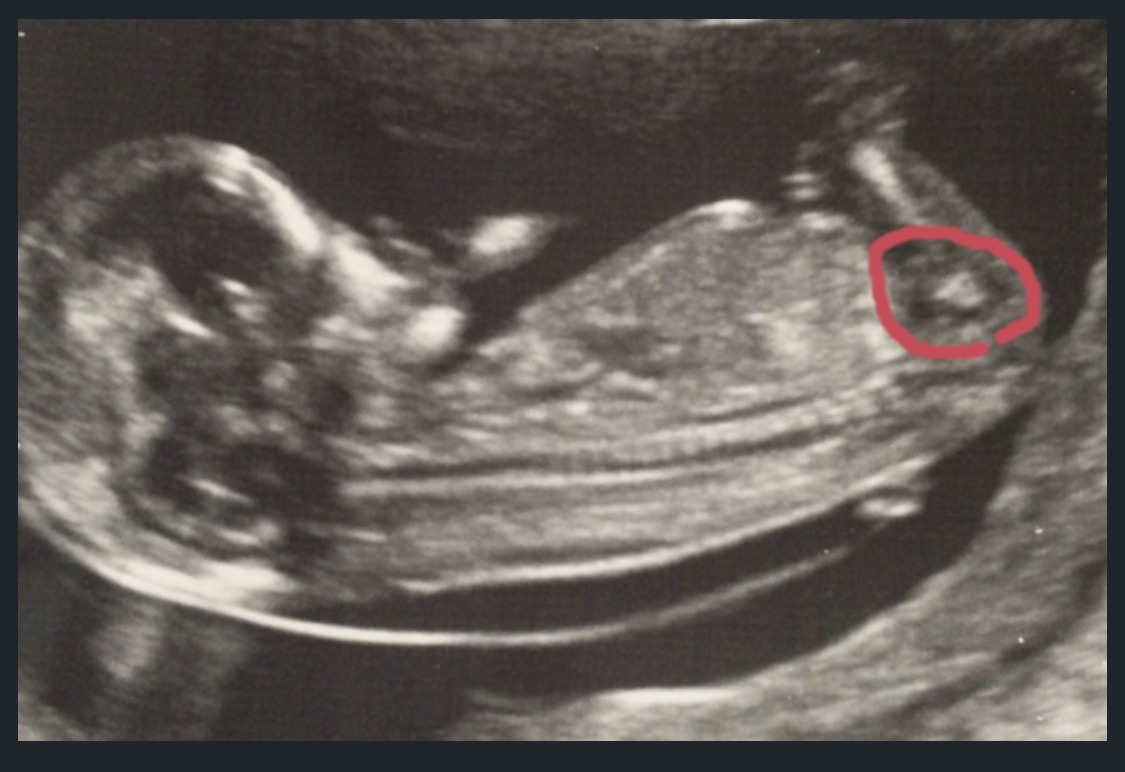

Hi my sister is 12 weeks and 6 days, i think i can see a forked nub there, what do you guys think the gender could be? thanks in advance x

im not sure but i think this may be a nub?

Attachment 27737